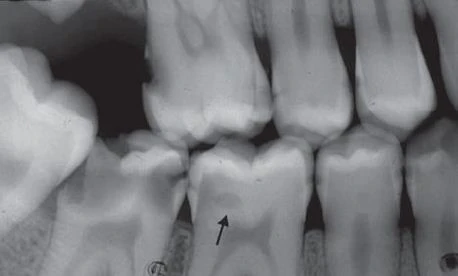

Thậm chí những nha sĩ nhiều kinh nghiệm cũng thường không đồng ý với việc có hay không có sâu răng khi kiểm tra trên một lần chụp X quang khi tổn thương chỉ giới hạn ở phần men răng. Đôi khi có thể phát hiện sai tổn thương sâu răng khi bề mặt răng không bị ảnh hưởng (kết quả dương tính giả). Nhiều hiện tượng hình thái chẳng hạn như những trũng và rãnh, chỗ lõm vùng cổ răng, hiệu ứng dải Mach, những bất thường về răng chẳng hạn như những rãnh giảm sản và những chỗ lõm do mòn răng cũng có thể giả dạng hình ảnh sâu răng. Trong những trường hợp mất khoáng không biểu hiện rõ trên X quang, việc không phát hiện được thương tổn được gọi là kết quả dương tính giả. Ngoài ra, những điểm tiếp xúc chồng lên nhau trên hình ảnh X quang có thể che lấp mất tổn thương. Khoảng một nửa tất cả những tổn thương mặt bên ở phần men răng không thể phát hiện được trên X quang.

Hình 10. Những hình ảnh dương tính giả (mũi tên)